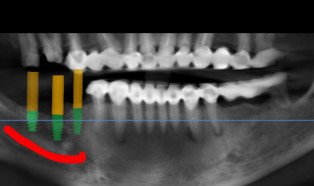

- 術前依照骨頭狀況評估植牙角度及位置

- 結合 3D電腦斷層影像分析,制訂詳細手術治療計畫,提前確定植牙深度、尺寸。讓手術過程中降低手術風險且大幅度提升植牙成功率

- 手術過程使用3D列印的高精準度導引板,不只增加手術的穩定性、安全性,減小手術傷口,減少疼痛,讓術後傷口復原時間更短,不影響日常生活及工作。